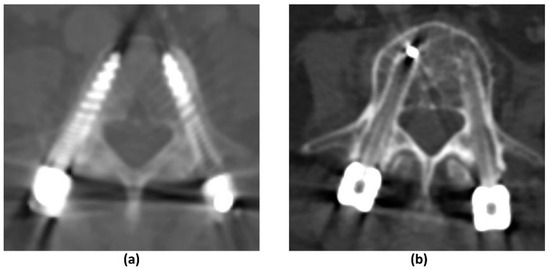

3.4.1. Challenges of CT: Metal-Related Artifacts

3.4.2. Photon-Counting CT